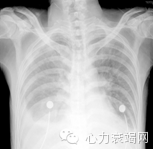

心脏扩大

二尖瓣中度关闭不全

三尖瓣中重度关闭不全

肺动脉高压